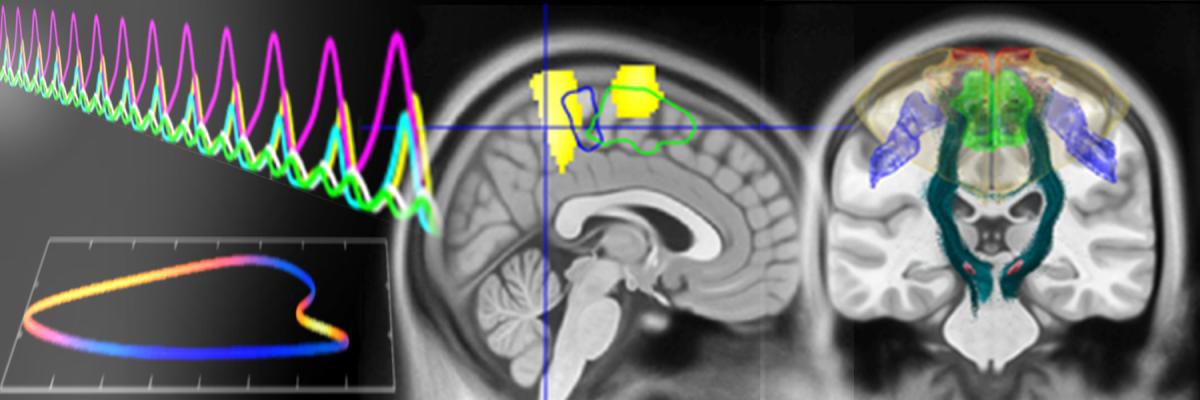

Image

stylised image of brain waves in several colours representing frequencies, and structure MRI brain scan images overlaid with brain regions shaded in colours.

Closed-loop approaches for impaired cognition and behavior